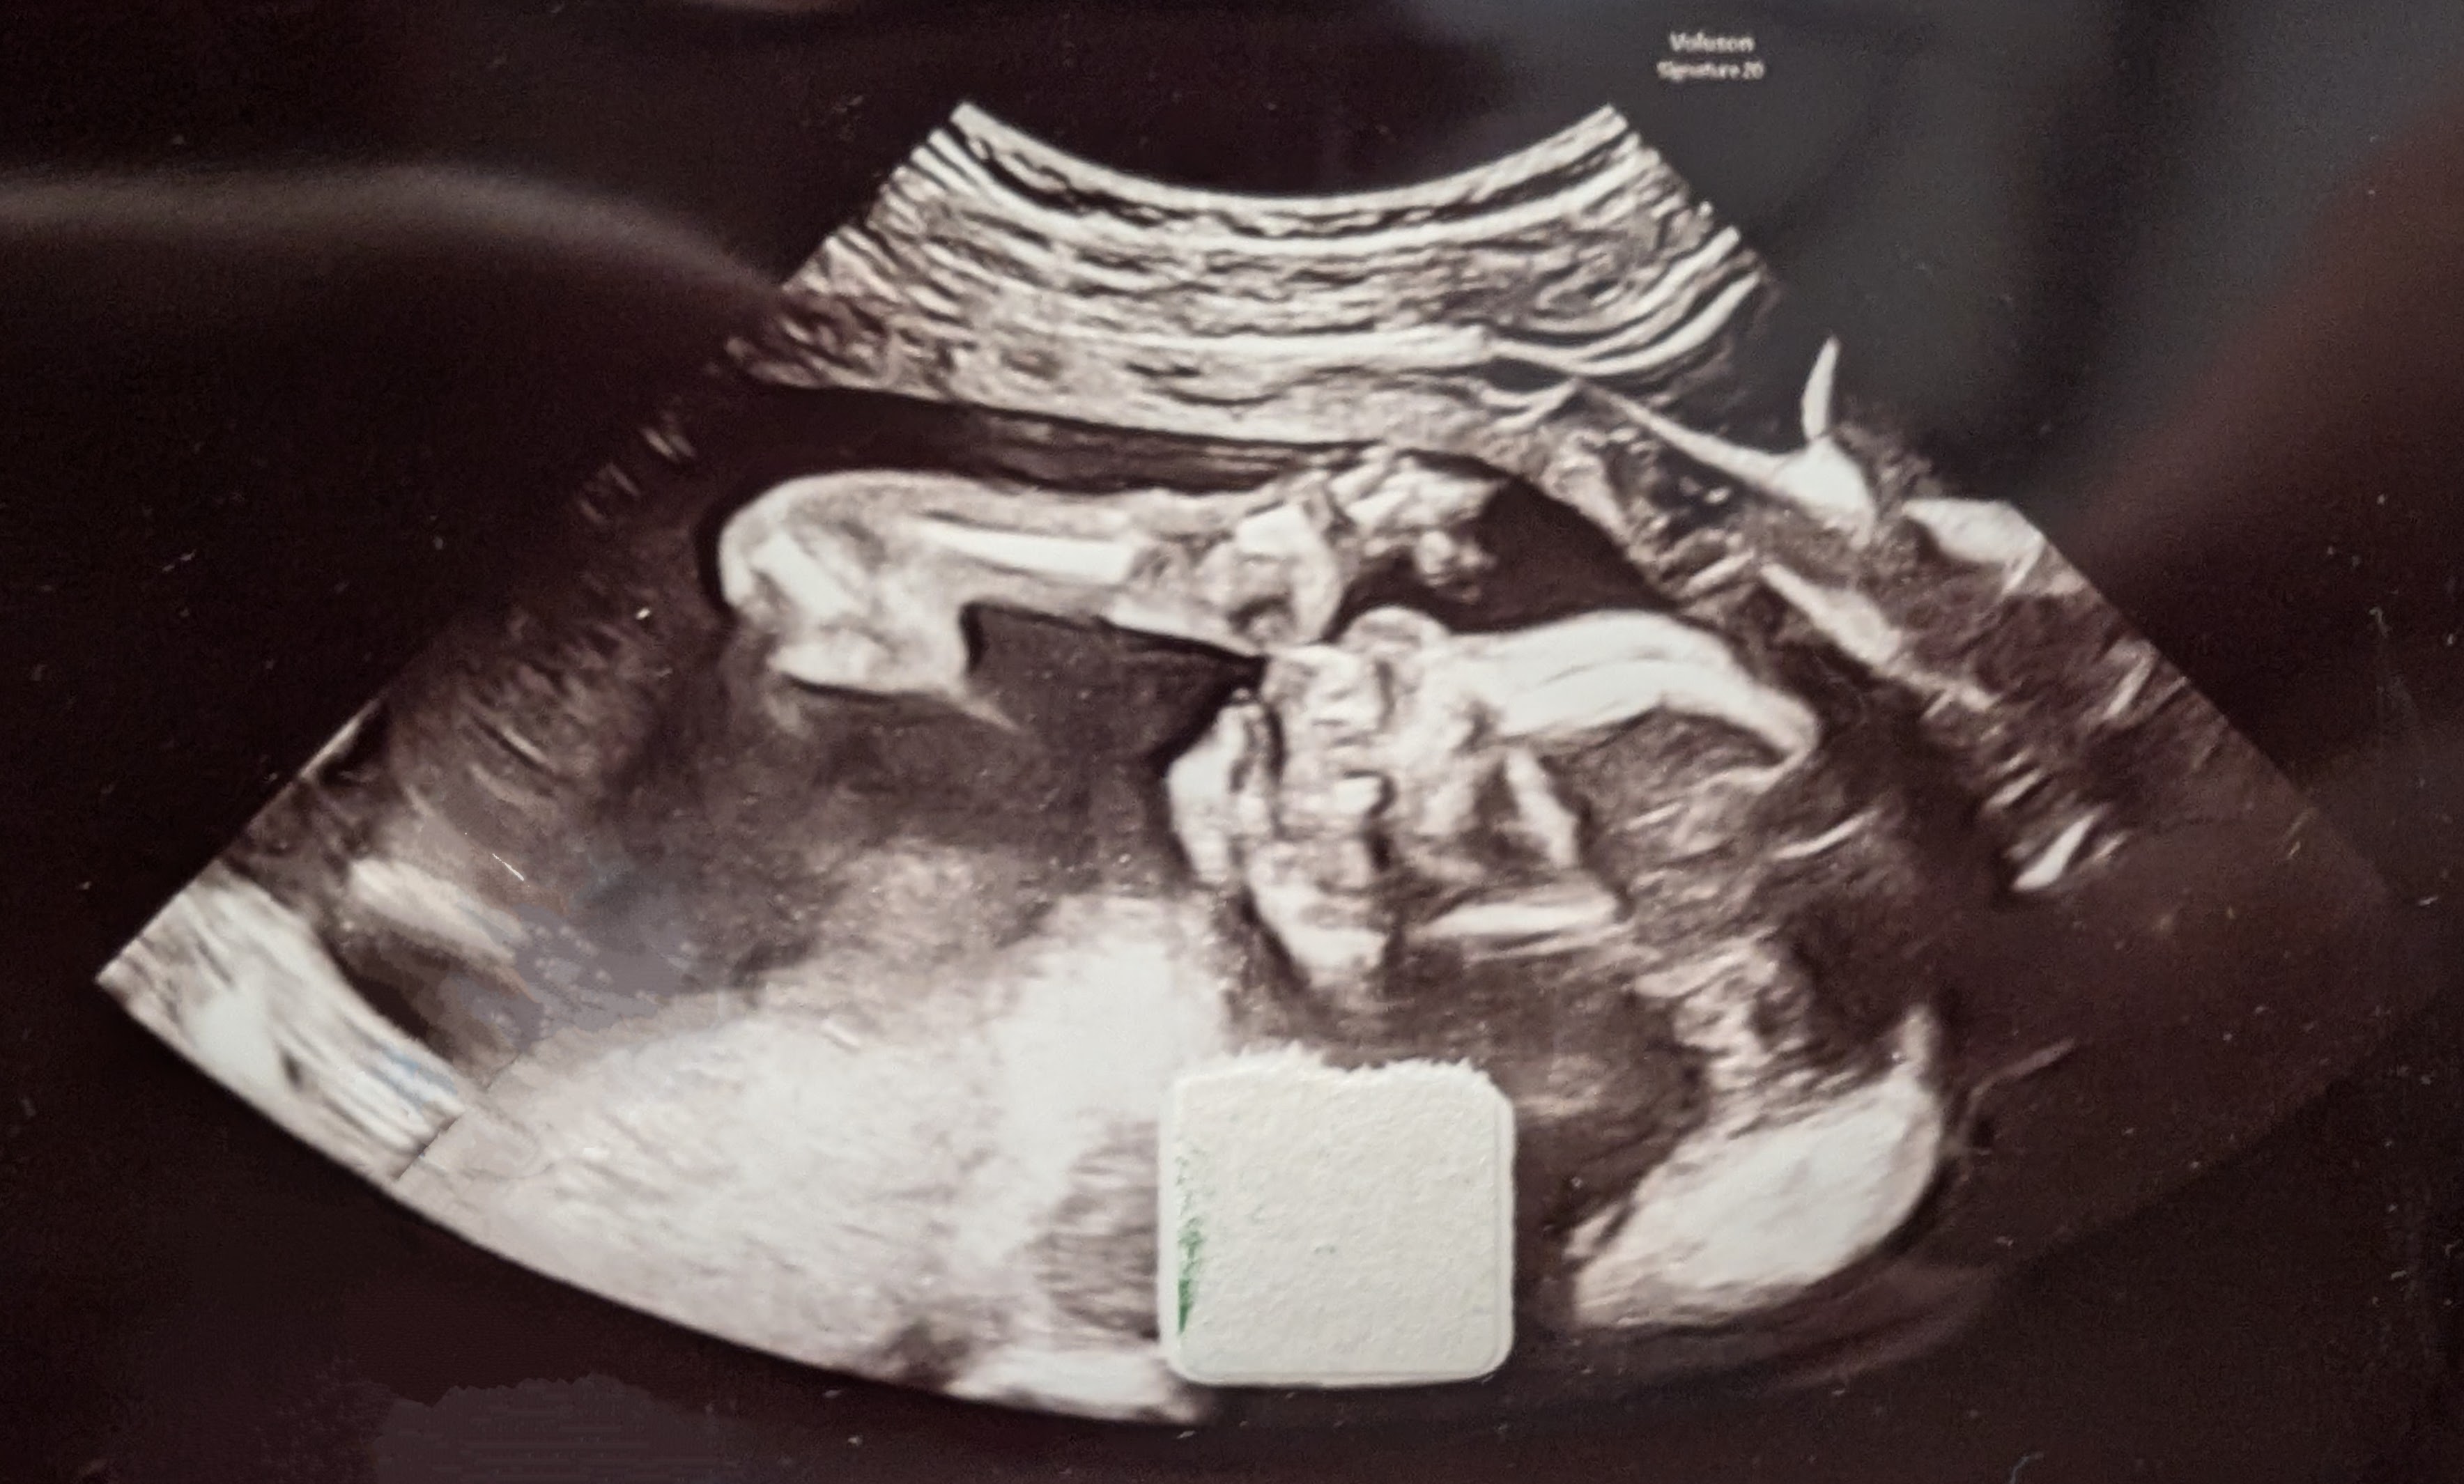

He's getting bigger! Pemi is now 22cm (8.5in) and weighs 223g (half a pound).